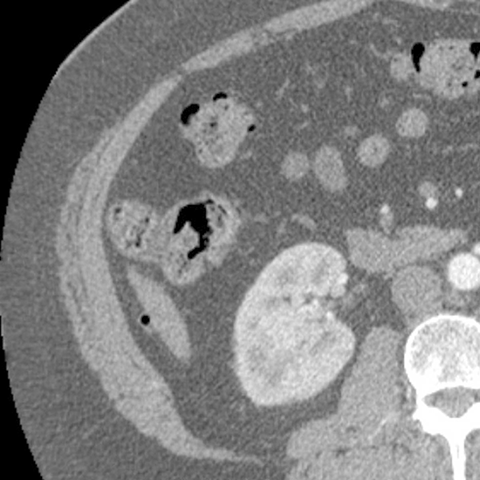

Normal Appendix, CT (axial) [4 of 6]